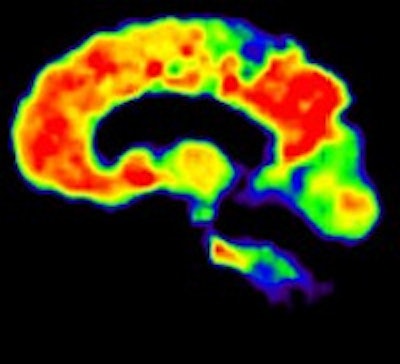

The image on the left shows PiB binding (red) in the cortical regions of the brain to indicate the presence of amyloid plaque, while the image on the right shows PiB binding to white matter (red), which signifies a negative result. All images courtesy of Dr. Rik Ossenkoppele.PiB-PET scans were positive in 40 (61%) of 66 patients with clinical Alzheimer's and in five (28%) of 18 patients with clinical frontotemporal dementia. FDG SUV patterns matched the clinical diagnosis in 58% of patients with Alzheimer's and 33% of patients with clinical frontotemporal dementia, the authors noted.